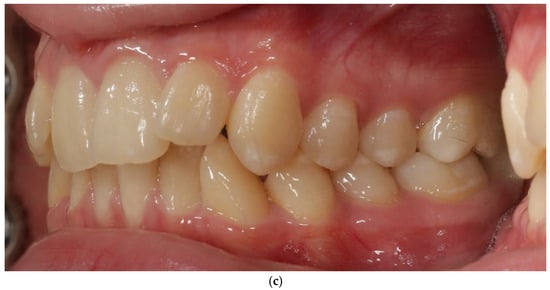

The vestibular soft-tissue phenotype appeared thicker, with reduced translucency and a more convex gingival contour. Gingival margin stability was maintained throughout therapy, and no recession, bleeding, or inflammation was present (Figure 4a–c). Outcome assessment in this case report is primarily qualitative and based on standardized clinical photography and clinical phenotype indicators (defined by periodontal probe transparency through the gingival margin), without quantitative soft-tissue thickness measurements.

Figure 4.

Patient 1 after treatment (a–c).

3.2. Patient 2—Soft-Tissue and Intra-Arch Control Outcomes

Because BPS was applied only in the maxillary arch, this patient provided an intra-arch control model under identical biological conditions. The maxillary BPS arch appeared to show features consistent with thickening of the vestibular phenotype, increased soft-tissue resilience, and reduced root translucency. In contrast, the mandibular control arch (treated with conventional biomechanics) appeared to retain a thin, translucent, and flattened phenotype. These qualitative clinical observations from both patients and both arches, including the intra-arch control, are summarized in Table 1.

Gingival phenotype was assessed using a standardized periodontal probe transparency test and evaluation of tissue resistance. No recession, pathological probing depths, or BOP were recorded. Although no ultrasonographic or transgingival thickness measurements were collected, the photographic changes were reproducible and consistent with recognized clinical indicators of phenotype thickening.